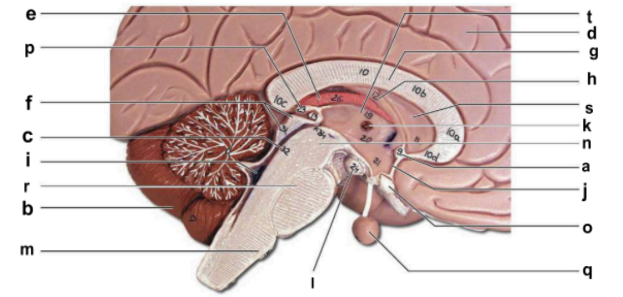

Identify the structure labeled “a” in the image.

anterior commissure

Identify the structure labeled “b” in the image.

cerebellum

Identify the structure labeled “c” in the image.

cerebral aqueduct

Identify the structure labeled “d” in the image.

cerebral hemisphere

Identify the structure labeled “e” in the image.

choroid plexus

Identify the structure labeled “f” in the image.

corpora quadrigemina

Identify the structure labeled “g” in the image.

corpos callosum

Identify the structure labeled “h” in the image.

fornix

Identify the structure labeled “i” in the image.

fourth ventricle

Identify the structure labeled “j” in the image.

hypothalamus

Identify the structure labeled “k” in the image.

interthalamic adhesion

Identify the structure labeled “l” in the image.

mammilary body

Identify the structure labeled “m” in the image.

medulla oblongata

Identify the structure labeled “n” in the image.

midbrain

Identify the structure labeled “o” in the image.

optic chiasma

Identify the structure labeled “p” in the image.

pineal gland

Identify the structure labeled “q” in the image.

pituitary gland

Identify the structure labeled “r” in the image.

pons

Identify the structure labeled “s” in the image.

septum pellucidum

Identify the structure labeled “t” in the image.

thalamus